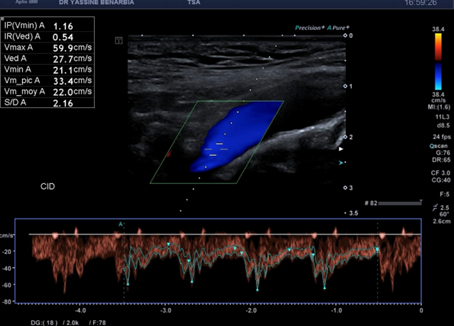

Du côté droit, l'examen met en évidence une dissection du tronc brachiocéphalique (TABC) avec présence d'un faux chenal circulant. Le flap intimal est clairement visible en mode B, séparant le vrai chenal du faux chenal. Au Doppler couleur, on observe un double flux avec des vélocités différenciées : le vrai chenal présente un flux rapide (codé en bleu qui s’éloigne de la sonde) tandis que le faux chenal montre un flux plus lent (codé en rouge qui se rapproche de la sonde).

Cette dissection s'étend à la carotide commune droite proximale. Le Doppler pulsé dans le vrai chenal montre un spectre triphasique conservé avec une vélocité maximale de 108,0 cm/s (normale) et un index de résistivité de 0,84 confirmant l'absence de retentissement hémodynamique. L'artère sous-clavière droite et l’artère vertébrale restent perméables avec des flux normaux au doppler.

Les signes retrouvés à l'échographie-Doppler sont : flap intimal mobile visible en mode B séparant vrai et faux chenal, double lumière artérielle en coupe transversale et longitudinale, flux différenciés au Doppler couleur (vélocités élevées dans le vrai chenal, flux plus lent dans le faux chenal), et spectre Doppler pulsé conservé dans le vrai chenal (triphasique ou biphasique).

Le faux chenal peut être circulant (flux présent, comme dans notre cas) ou thrombosé (sans flux). Un faux chenal circulant stable sans sténose hémodynamique est de bon pronostic sous surveillance.

Les critères de stabilité à surveiller sont : taille du faux chenal inchangée, flux conservé dans le vrai chenal avec vélocimétrie normale (Vmax < 125 cm/s), absence d'extension de la dissection, absence de thrombose progressive, et absence de dilatation anévrysmale.